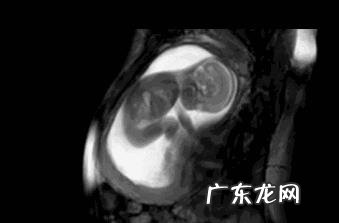

胎儿在子宫内伸手、踢腿、冲击子宫壁的话就会造成胎动 , 经产妇怀孕满4个月后 , 准妈妈就能够非常清楚地感受到胎儿的活动 , 初产妇一般是做5个月 , 甚至更晚 , 孕6 个月才可以感受到胎动 。胎动的次数多少、快慢强弱等与胎儿的生长情况都是有关系的 。

但是感觉到胎动的早晚也有个体差异 , 如孕妇肚皮的厚薄 , 薄的感受到胎动会早一些 , 羊水的多少 , 羊水少的孕妇感受到胎动会更早 , 孕妈的敏感度? , 敏感的麻麻能更早感受到胎动 。